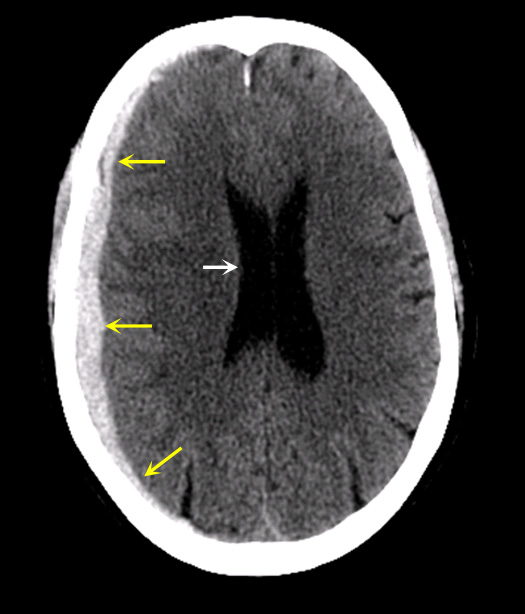

Case 2:

Imaging findings:

Figure 2: Pre-contrast CT

- Patient with history of recent fall.

- Acute subdural hematoma covering the right cerebral hemisphere (yellow arrows) is seen.

- Blood in acute stage appears hyperdense in pre-contrast CT scan.

- Acute subdural hematoma is crescentic in shape (yellow arrows). Medial margin is not convex as in the epidural hematoma.

- Acute blood is hyperdense (CT density 30-80 HU).

- Acute subdural hematoma crosses suture lines, thus spreads diffusely over the brain surface (yellow arrows).

- Can cause significant mass effect with midline shift leading to brain herniation. White arrow points to mild compression of the right lateral ventricle with slight midline shift.